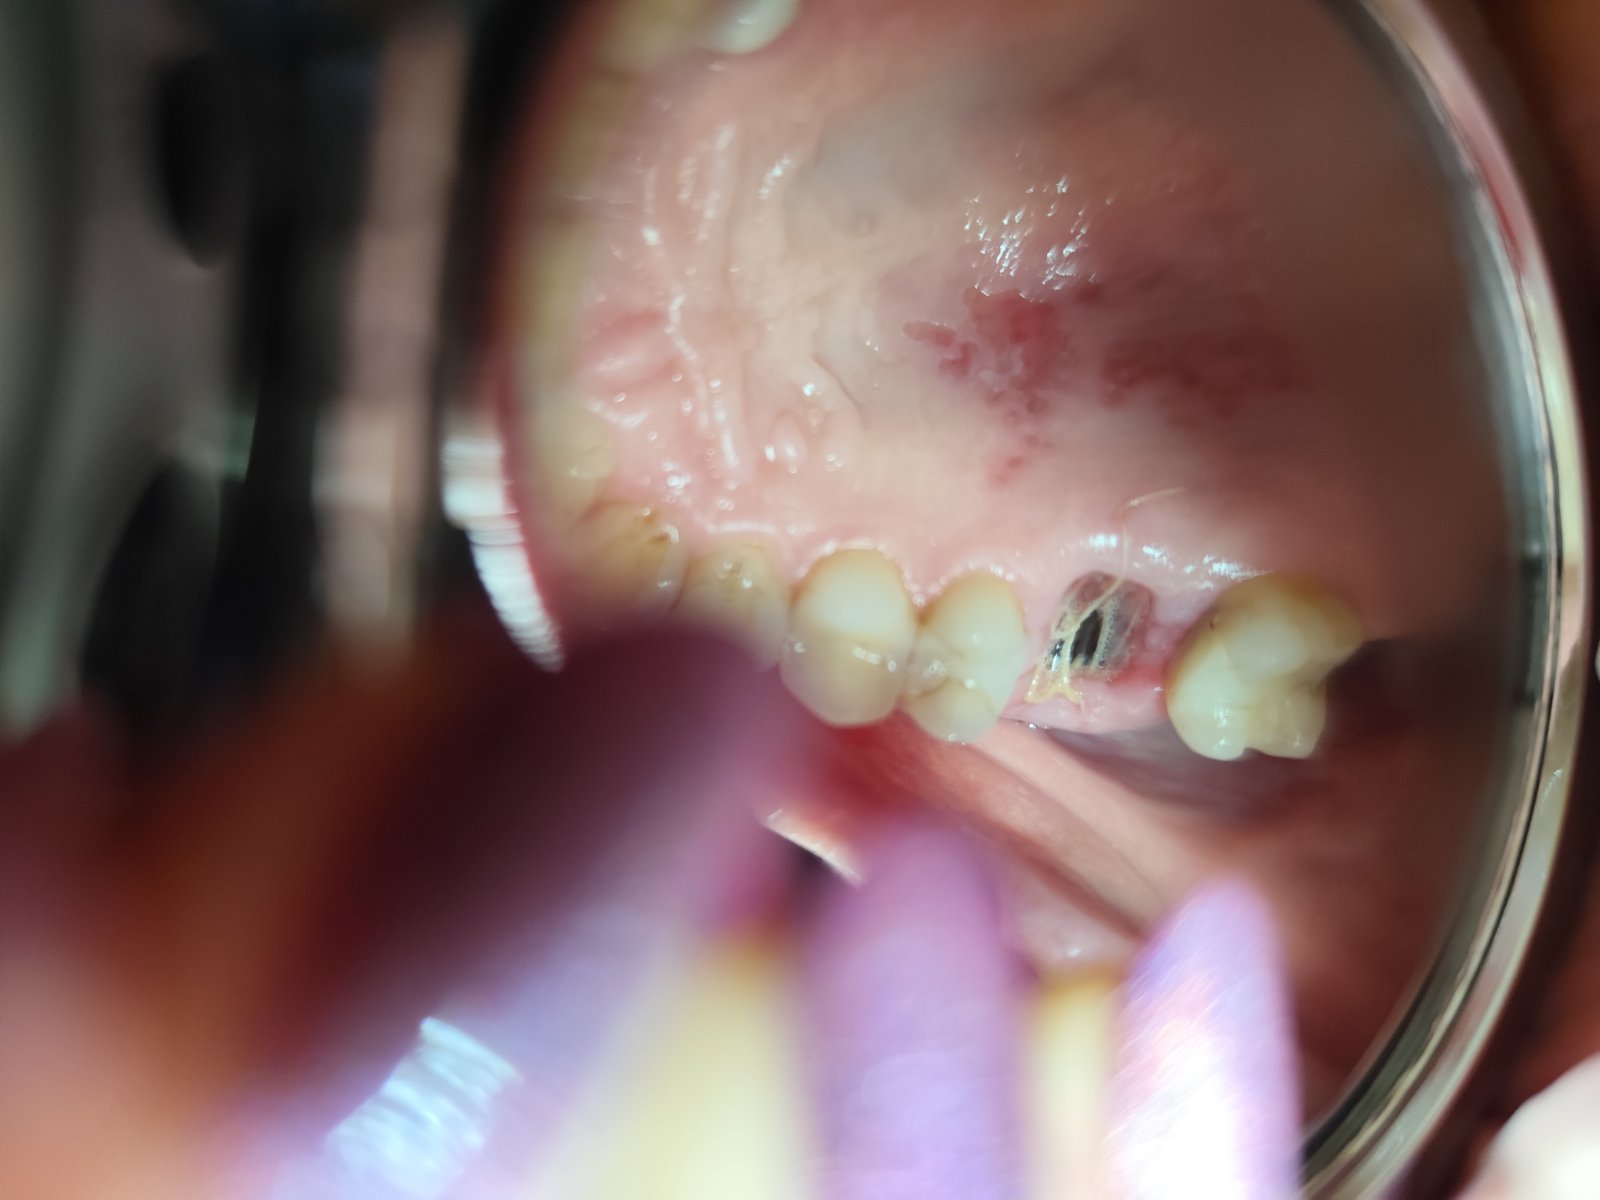

Ahojte. Potrebujem poradit ci mate skusenost. Som 4 den po vythnuti zuba kde bol zapal uz v koreni po 15 rocnom osetreni kanalikov. Chcem vediet ci sa to hoji dobre podla fotky. Stale mam take divne pocity okolo 5 dasna plus sa mi na 2 den spravili afty na podnebi alebo co to je? Ranu si jemne vyplachujem od 2 dna meridolom bez alkoholu. Ranu mam aj situ som bez antb. Nie je to prilis velka diera?